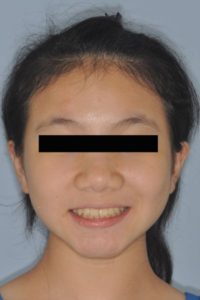

今天和大家分享一個案例

12歲的劉小妹 希望把 前牙排列整齊 快速矯正的案例

可以看到劉小妹側面外觀不錯 所以我們決定以 不拔牙 方式來排列牙齒

矯正完牙齒排列整齊 咬合更加良好 笑容也更燦爛了!